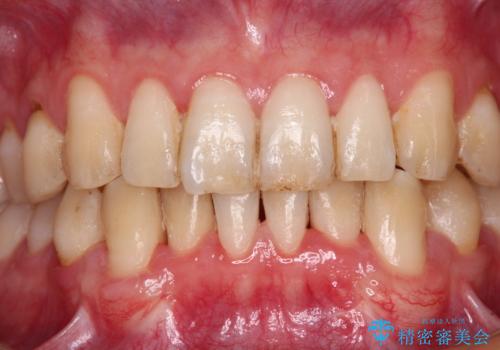

前歯は着色や虫歯治療の跡が目立っている状態で、オールセラミッククラウンによる審美治療を希望されていました。

歯肉が非常に菲薄であり、オールセラミッククラウンを装着後の近い将来歯肉退縮によりセラミックの境目が見えてくることが懸念されました。